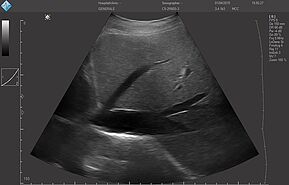

E-FAST (расширенный-FAST) дополнительно обследует переднюю и боковую плевральную полость (торакальная проекция) для оценки наличия пневмоторакса или плеврального выпота, предположительно гемоторакса у пациентов с травмой.

E-FAST имеет высокую чувствительность и специфичность (особенно в условиях гипотонии), может быть выполнен быстро, неинвазивно, без лучевой нагрузки, и может проводиться повторно. Благодаря таким преимуществам ультразвук по существу заменил диагностический перитонеальный лаваж (ДПЛ) при обследовании пациентов с травмой.

Положительный E-FAST у гемодинамически нестабильного пациента может указывать на необходимость проведения немедленного вмешательства (например, зондовой торакостомии, перикардиального окна, диагностической лапаротомии).